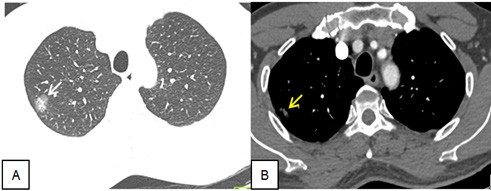

Qua tham khảo phim CT ngực không tiêm thuốc cản quang từ bệnh viện tuyến trước gửi đến, BN được chỉ đӏnh chụp CLVT ngực bằng máy 64 dãy, có tiêm cản quang tĩnh mạch. Chi tiết được thể hiện trong hình 1.

Hình 1. Phim CT ngực bệnh nhân khi vào viện. A (cửa sổ nhu mô): Nốt kính mờ, kích thước 18 x 16mm; trong có phần lõi đặc, kích thước 8×6 mm (mũi tên trắng). B (cửa sổ trung thất sau tiêm cản quang): quan sát thấy phần lõi đặc của nốt kính mờ (mũi tên vàng)